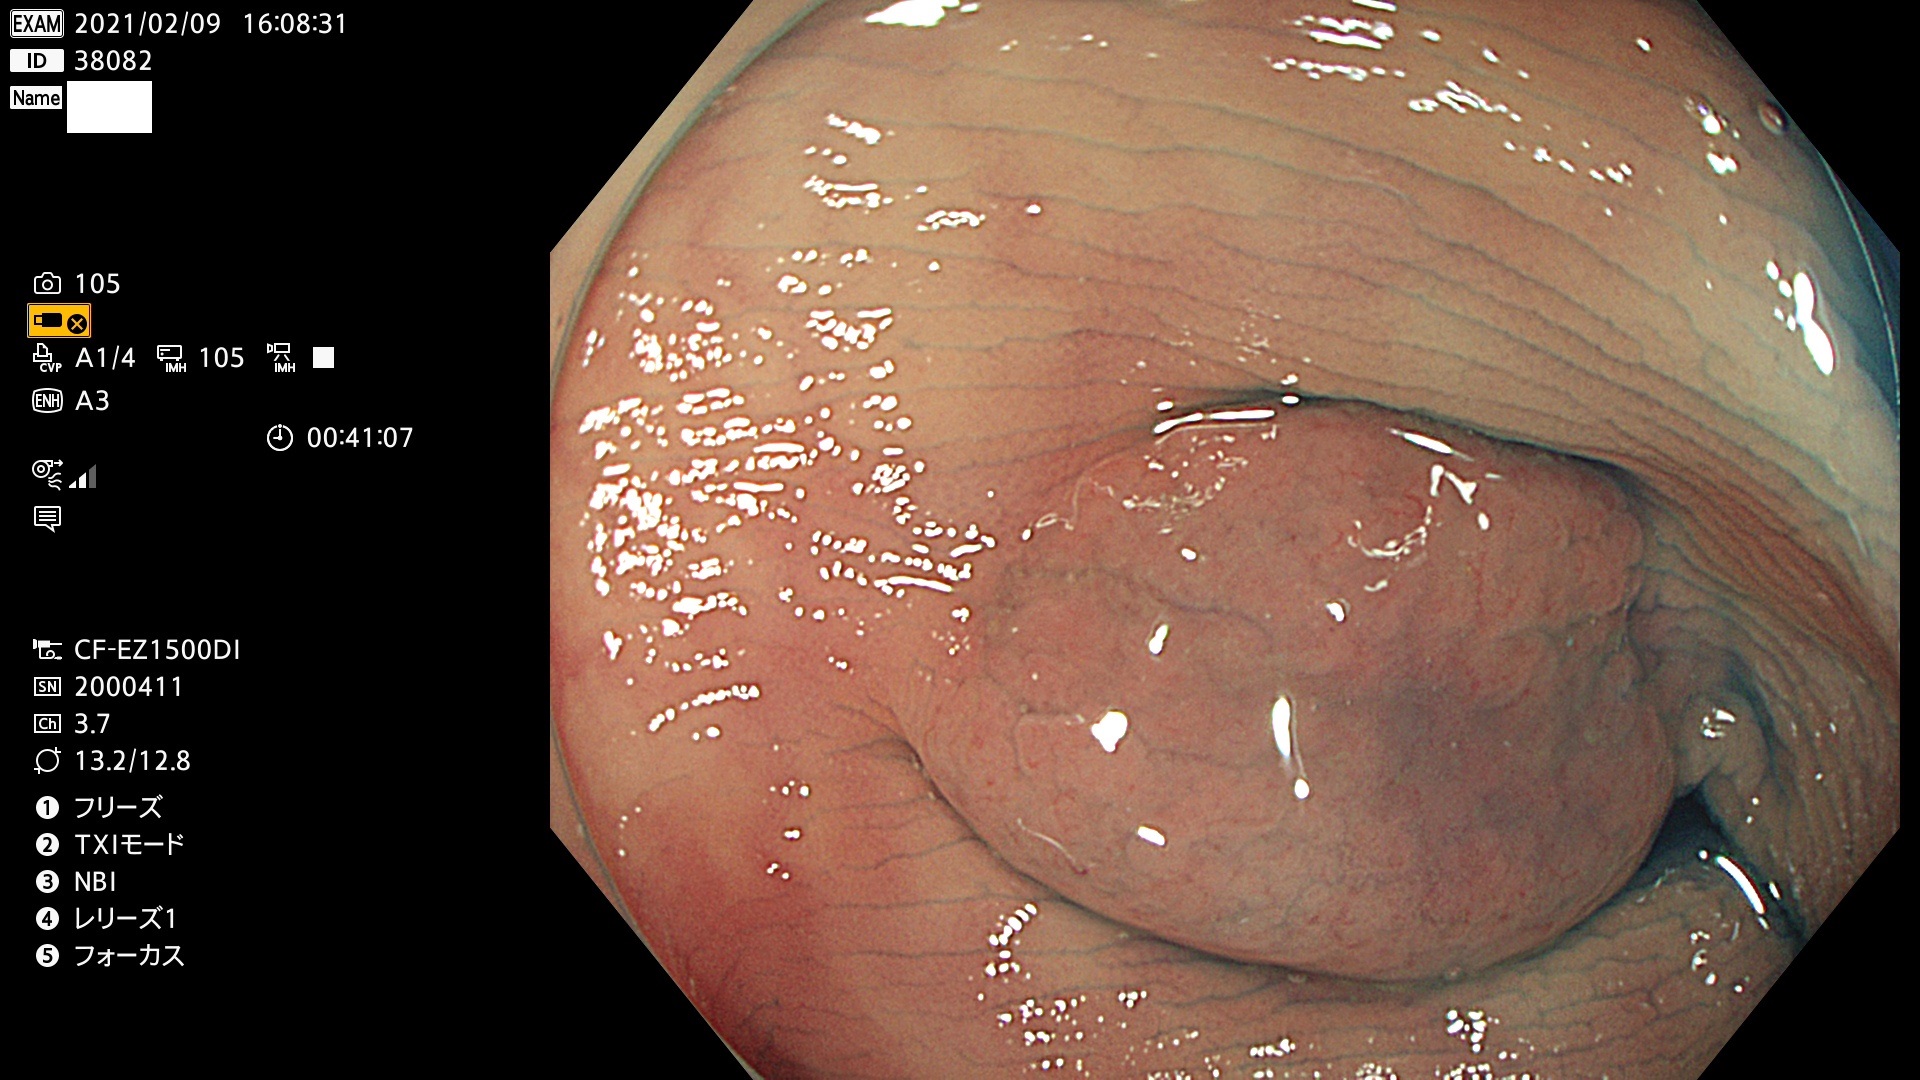

38001 38002 38003 38004 38006(SSAPのみ) 38007 38008 38009 38010 38012 38013 38014 38016 38018 38020 38021 38025 38026 38029 38032 38033 38034 38035 38036 38037(SSAPのみ) 38039 38043 38044 38048 38049 38050 38052 38055 38056 38057 38058 38059 38064(SSAPのみ) 38065 38068 38069 38070 38071 38072 38074 38075 38076 38078 38079 38080 38082 38083 38084 38085(SSAPのみ) 38086 38087 38088 38089 38090 38091 38092 38093 38094 38097 38098 38099

発見困難で危険性の高い平坦型病変(上記100名より抽出)